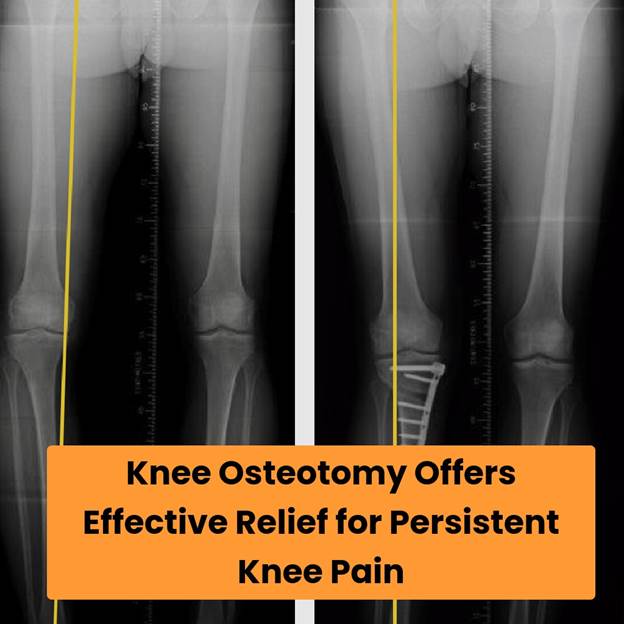

Knee pain is a common issue that can severely affect daily life, limiting movement and causing discomfort. Causes can range from arthritis to injuries, significantly impacting one’s mobility. Knee osteotomy emerges as a viable solution for many looking to alleviate this pain and regain normal function. This procedure repositions the bones around the knee to shift the load away from the damaged area, ultimately improving joint alignment and function.

https://trycom.s3.amazonaws.com/blog_imgs/cf69d676-0d68-41e5-bc8c-36bd5a542fc7.pngThree primary types of knee osteotomy procedures include high tibial, distal femoral, and tibial tubercle osteotomies.